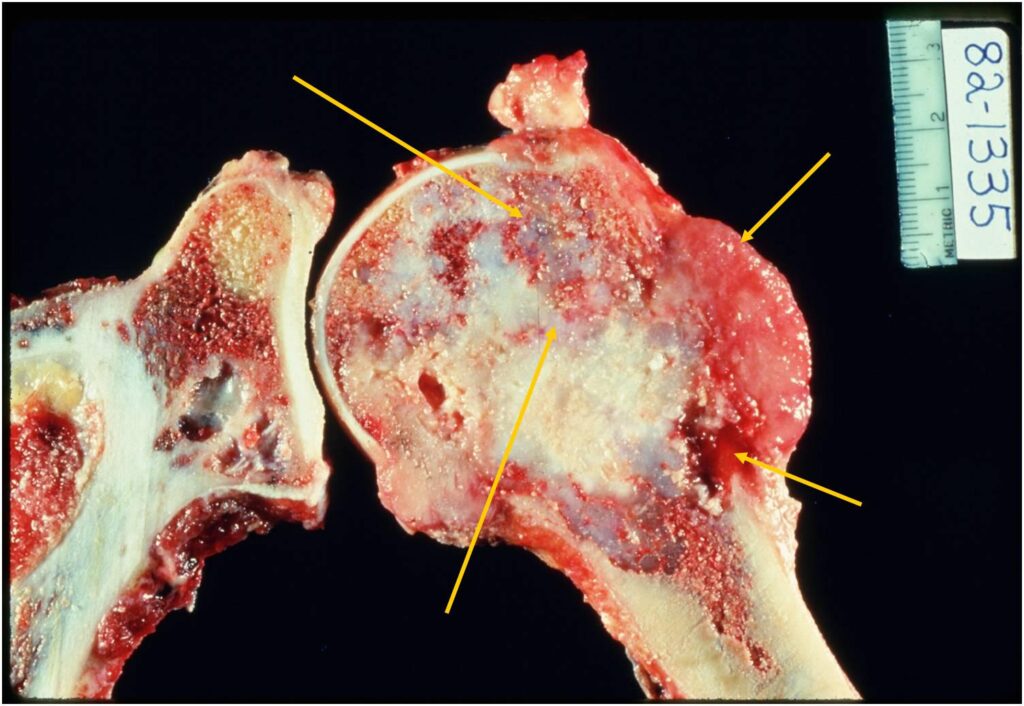

Gross Pathology

- Areas with typical lobular, blue-gray myxoid hyaline cartilage tissue

- Or overtly cartilaginous appearance of mature hyaline cartilage

- Zones of brown, tan, or hemorrhagic tissue

- Lacking the consistency of cartilage

- Dedifferentiated component may only be a minor portion of the overall tumor

- May also be so extensive that little cartilage is recognizable

(Top Arrow) High Grade Dedifferentiated Spindle Cell Sarcoma Component

(Left Arrow) Low Grade Cartilage Component

(Right Arrow) Low Grade Cartilage Component